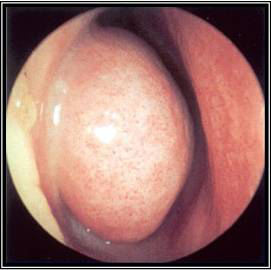

აუცილებელია ცხვირის ღრუს შემოწმება ლორწოვანი გარსის ერითემის ან ჩირქოვანი გამონადენის არსებობაზე. ოპტიმალური შემოწმების ჩატარება შესაძლებელია შეშუპების საწინააღმდეგო სპრეის ლოკალური დატანების შემდეგ.[17] როგორც ოტოსკოპი, ისე ნაზალური სარკე და რეფლექტორული განათება შეიძლება იყოს გამოყენებული. ცალმხრივი ჩირქოვანი გამონადენი, ლორწოვანი გარსის შეშუპება ან ერითემა, აგრეთვე სახის არეში მტკივნეულობა მიანიშნებს ბაქტერიული სინუსიტის არსებობაზე. არაჩირქოვანი გამონადენი საფიქრებელს ხდის ვირუსული ან ალერგიული ანთების არსებობას. იმის გათვალისწინებით, რომ ნაზალური გასინჯვა შესაძლოა იყოს გაძნელებული, ან ავლენდეს მხოლოდ არა-სპეციფიურ ნიშნებს, ცალკეული პაციენტებისთვის რეკომენდებულია ნაზალური ენდოსკოპიის ჩატარება, კერძოდ, ემპირიული ანტიბიოტიკოთერაპიის მიმართ რეფრაქტერული პაციენტებისთვის, როდესაც არსებობს ეჭვი ანტიბიოტიკებისადმი რეზისტენტობაზე, ან პაციენტი არის იმუნოკომპრომენტირებული.

ენდოსკოპია იძლევა ცხვირის ღრუს და სინუსების სადრენაჟე გზების საუკეთესო ვიზუალიზაციის საშუალებას. არსებობს ორი ტიპის ენდოსკოპი: რიგიდული და ელასტიური. რიგიდულ ნაზალურ ენდოსკოპს უკეთესი რეზოლუცია გააჩნია და მისი მართვა ცალი ხელით შეიძლება. ეს აადვილებს საჭიროების შემთხვევაში კულტურების მიღებას ცხვირის ღრუდან ან წიაღიდან. ელასტიური ნაზალური ენდოსკოპი პაციენტებისთვის უფრო კომფორტულია, მაგრამ მისი მართვა ორივე ხელის დახმარებით ხდება. არსებობს დრეკადი ცხვირის ენდოსკოპი, რომელსაც აქვს კულტურის შეგროვების არხი, მაგრამ უფრო დიდი და არასასიამოვნოა და მათი დამუშავებაც უფრო რთულია. ზოგადად, დრეკადი ენდოსკოპის გამოყენება უმჯობესია ბავშვთა ასაკში მისი კარგი ამტანობის გამო; თუმცა როგორც მოზრდილების, ისე ბავშვთა გამოსაკვლევად შესაძლებელია ორივე ტიპის ენდოსკოპის გამოყენება. არჩევანი დამოკიდებულია შემსრულებლიექიმის გამოცდილებაზე და შემთხვევათა უმეტესობაში იშეიძლება ჩაატაროს ყელ-ყურ-ცხვირის სპეციალისტმა.

[Figure caption and citation for the preceding image starts]: მარჯვენა შუა ნიჟარა და შუა გასასვლელი ხილვადია შეშუპების საწინააღმდეგო სპრეის დატანების შემდეგექ. Melissa Pynnonen-ის კოლექციიდან [Citation ends].